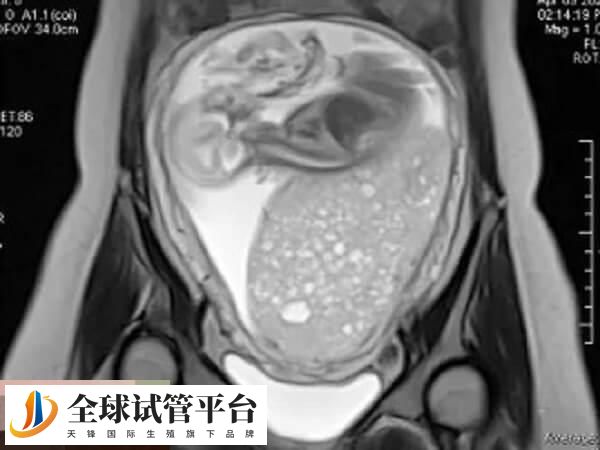

做三代试管婴儿会不会有葡萄胎

虽然三代试管移植前会进行胚胎筛查,一般医生会建议曾经有过葡萄胎经历的患者将胚胎发育到囊胚后再做筛查,确认染色体没有问题再移植,这样就能有效预防葡萄胎。但是葡萄胎的形成也不止由胚胎决定,所以三代试管无法完全避免。

而且要注意的是,葡萄胎出现的几率是不可控的,人为只能降低患有葡萄胎的风险,而没有办法做到0风险,但如果是从备孕的时候就开始对葡萄胎的风险进行控制,怀孕后出现这种情况的几率是很少的,如果说做试管的女性想要降低出现葡萄胎的几率,不妨选择在移植前对胚胎进行检查,这样能降低风险。